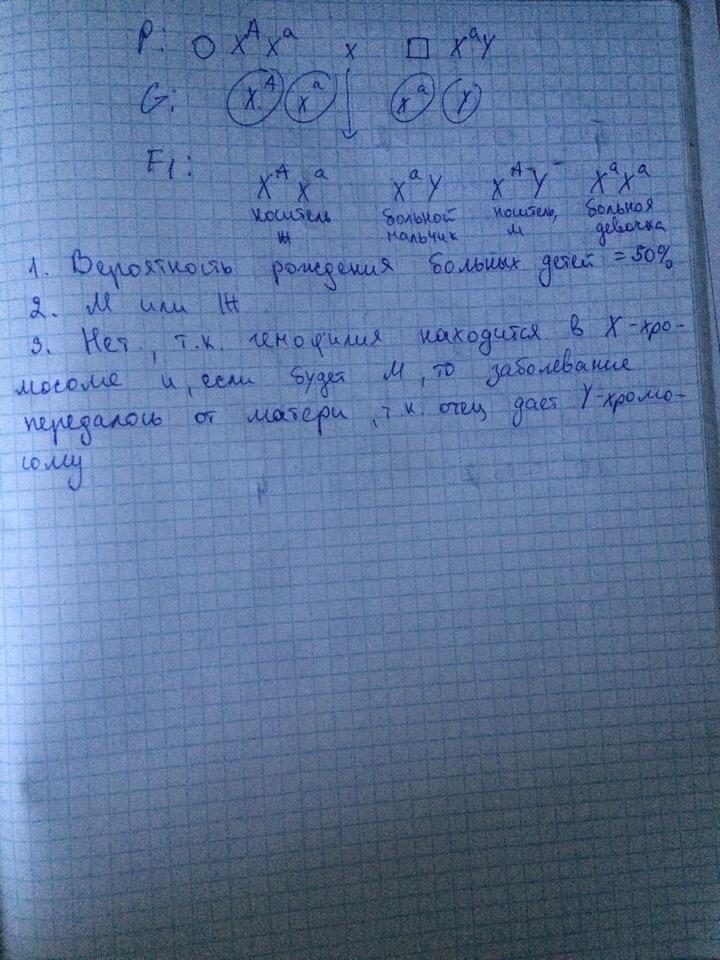

Генетика гемофилии: рецессивные гены и их проявления